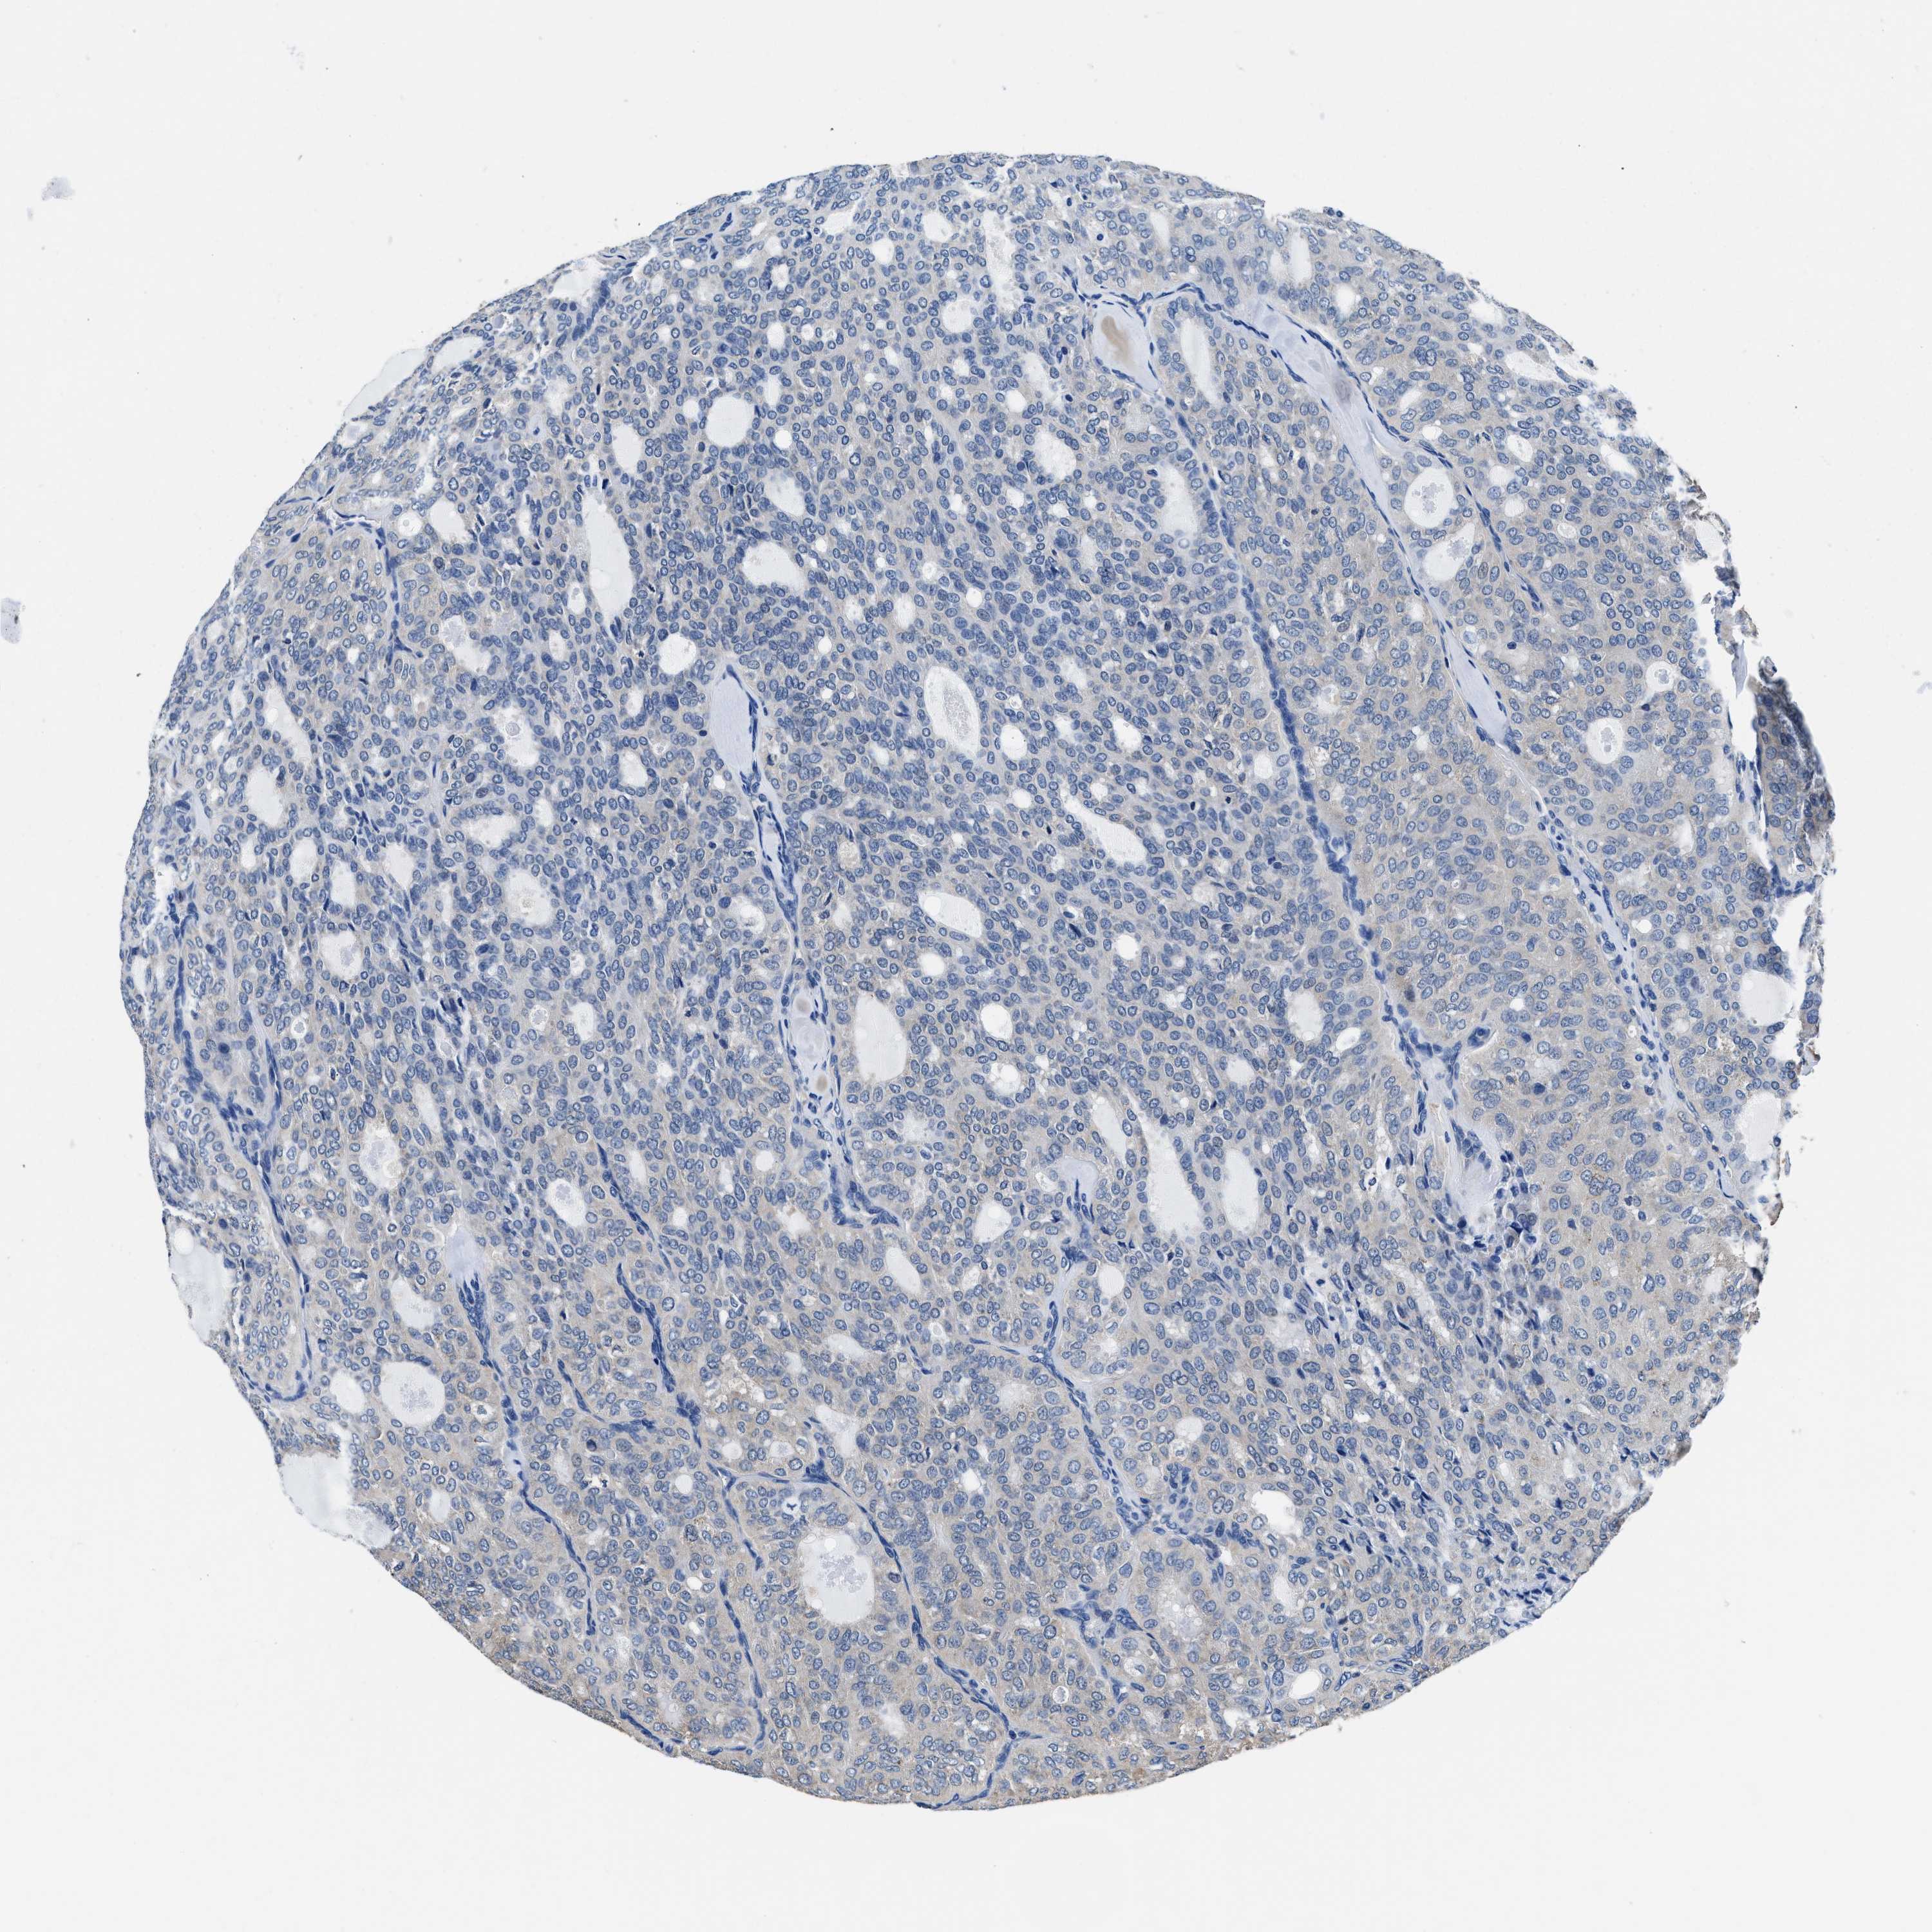

THYROID CANCER - Protein expressioni

A mouse-over function shows sample information and annotation data. Click on an image to view it in a full screen mode. Samples can be filtered based on level of antibody staining by selecting one or several of the following categories: high, medium, low and not detected. The assay and annotation is described here.

Note that samples used for immunohistochemistry by the Human Protein Atlas do not correspond to samples in the TCGA dataset.

Antibody stainingi

Antibody staining in the annotated cell types in the current human tissue is reported as not detected, low, medium, or high, based on conventional immunohistochemistry profiling in selected tissues. This score is based on the combination of the staining intensity and fraction of stained cells.

Each image is clickable and will lead to virtual microscopy that enables deeper exploration of all samples and also displays staining intensity scores, fraction scores and subcellular localization as well as patient and tissue information for each sample.

Antibody HPA015634

Antibody HPA021506

Staining

High

Medium

Low

Not detected

Intensity

Strong

Moderate

Weak

Negative

Quantity

>75%

75%-25%

<25%

None

Location

Nuclear

Cytoplasmic/membranous

Cytoplasmic/membranous,nuclear

Papillary adenocarcinoma, NOS

Follicular adenoma carcinoma, NOS